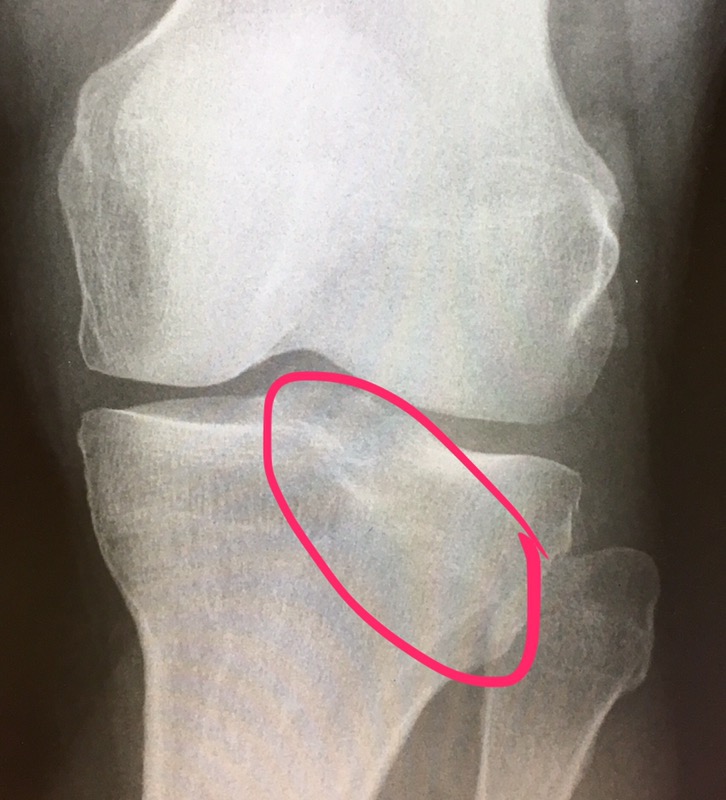

Got hit by van the other day. Can you believe it? The know-it-alls say that that line of distortion in the X-ray could (could!) be a tibial plateau fracture. Yea. The van hit my left knee.